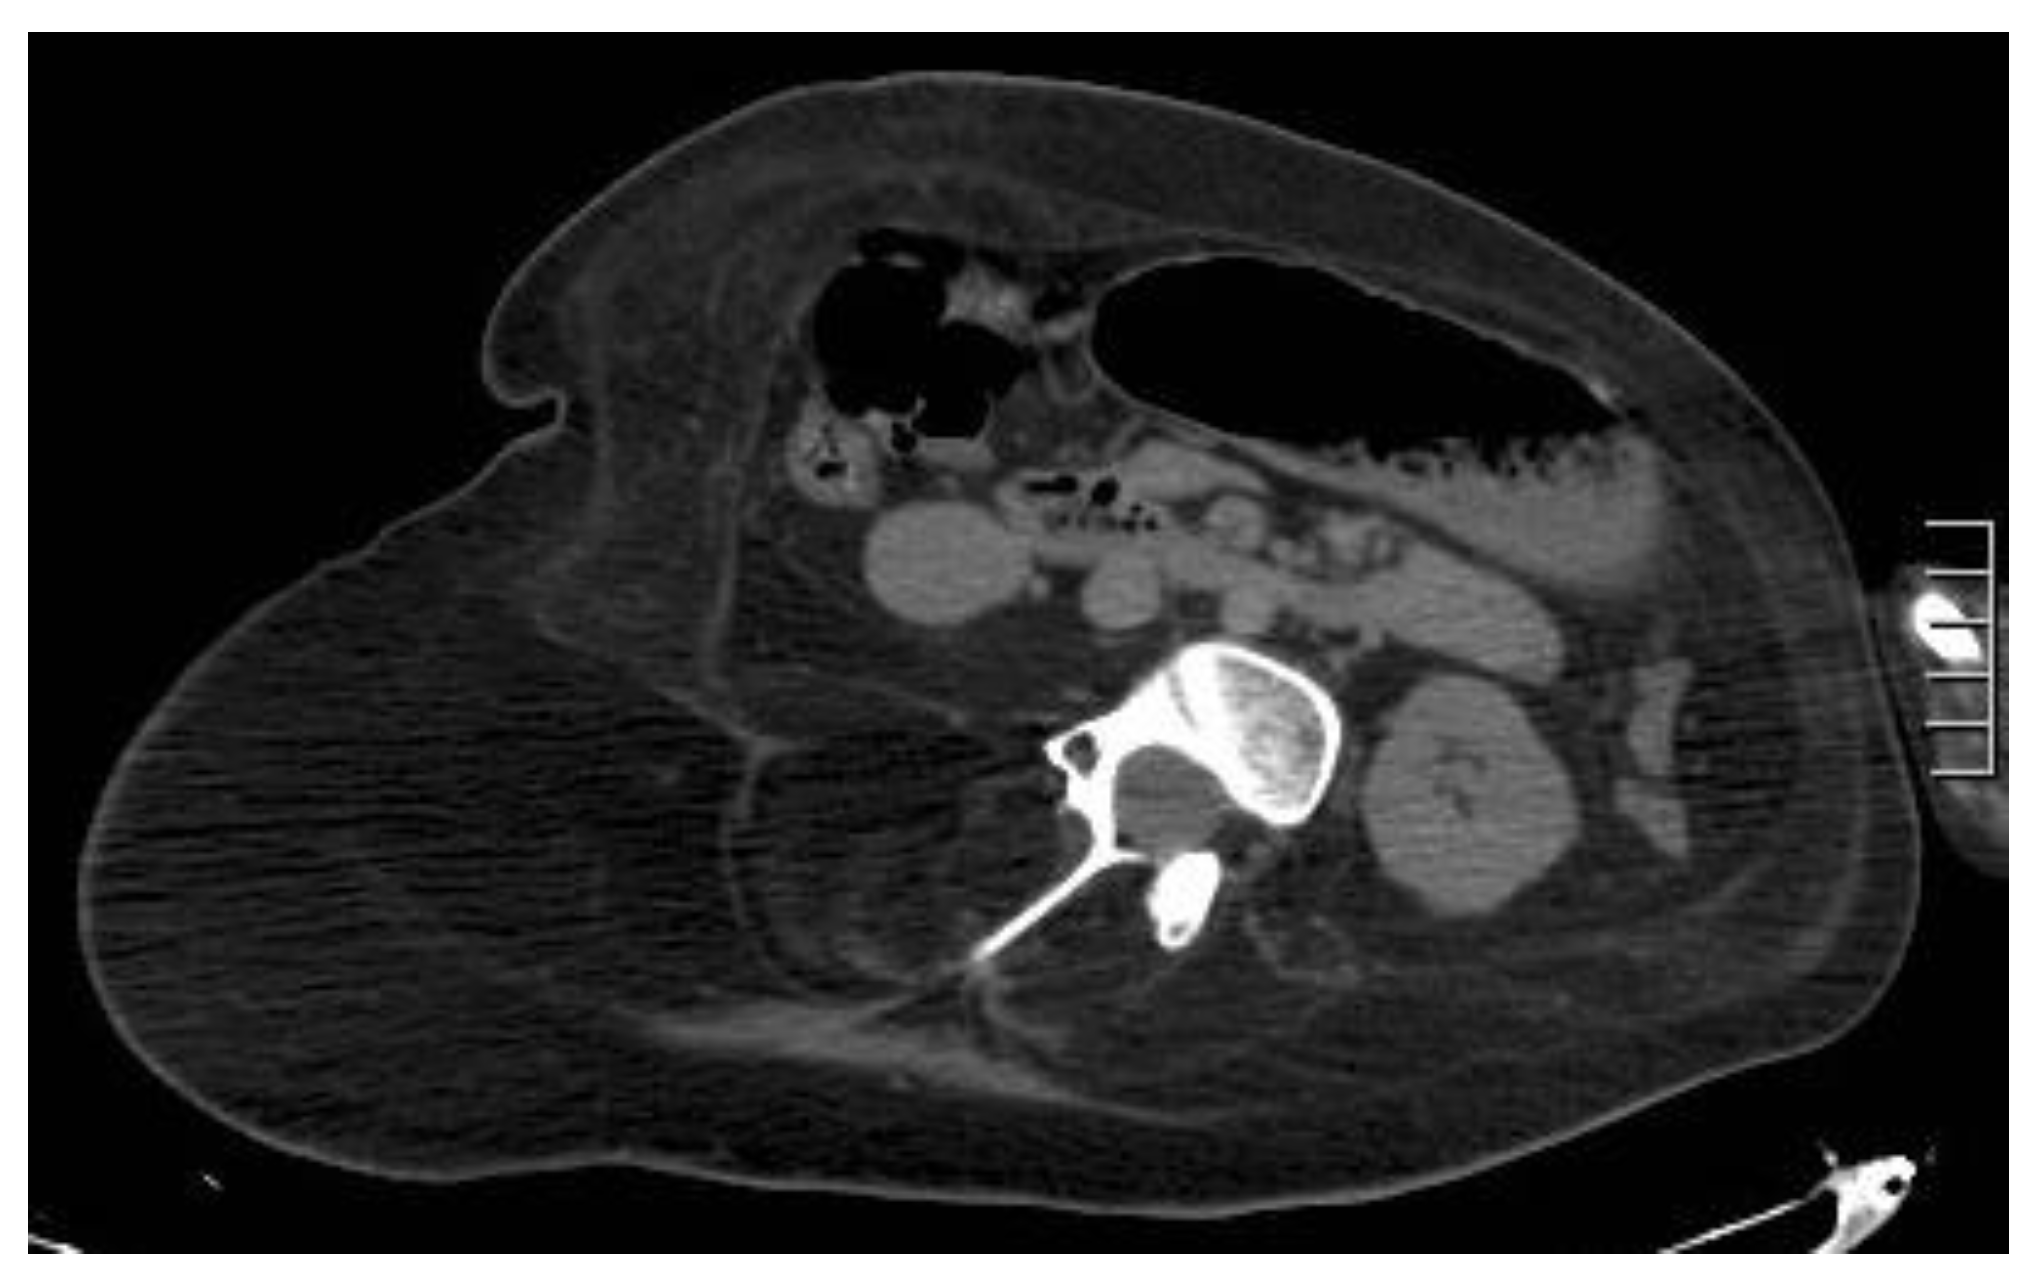

Figure 7. A 23-year-old patient with Duchenne’s syndrome. Axial, not-enhanced CT scan demonstrates complete fat replacement of all abdominal wall muscles with obligated decubitus, as commonly seen in cases of Duchenne’s syndrome patients reaching the ages of 20–30.